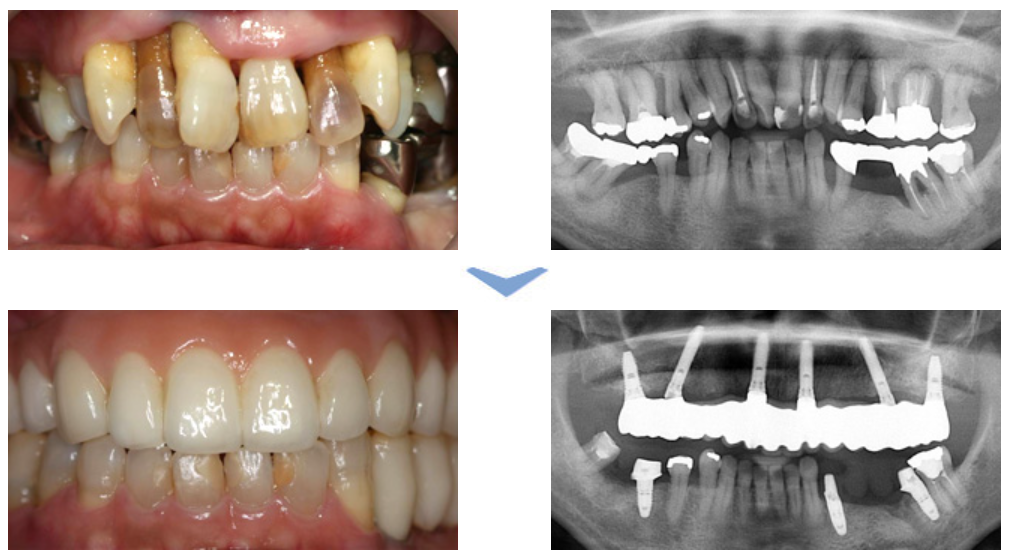

実際に施術した患者様の一例です 実際に施術した患者様の一例です

大竹歯科クリニックでは、最新の技術を駆使した安全で確実なインプラント治療を提供しています。特に注目すべきは、光機能化処理を施したインプラントの使用です。

この革新的な技術はチタンエイジング現象を克服し、インプラントの性能を最大限に引き出します。特定波長の紫外線照射により、インプラント表面の生体親和性が回復し、骨細胞の成長・分化速度が3倍に加速されます。

その結果従来50%程度だった骨接触率が98%以上に向上し、治療期間の短縮とインプラント生存率の大幅な改善が実現しました。また高精度X線CT撮影装置の導入により、より精密な診断と安全な治療が可能となりました。

大竹歯科クリニックのインプラント治療は詳細な診断から手術、そしてメンテナンスまで、一貫した丁寧なケアを提供します。患者様の口腔の健康と機能回復を最優先に考え、最新の技術と豊富な経験を活かした治療を行っています。